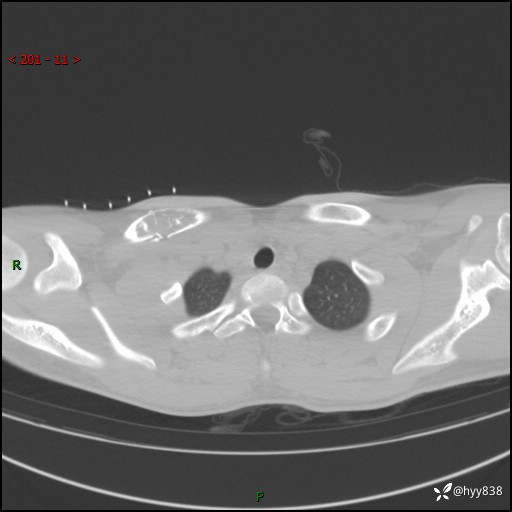

CT